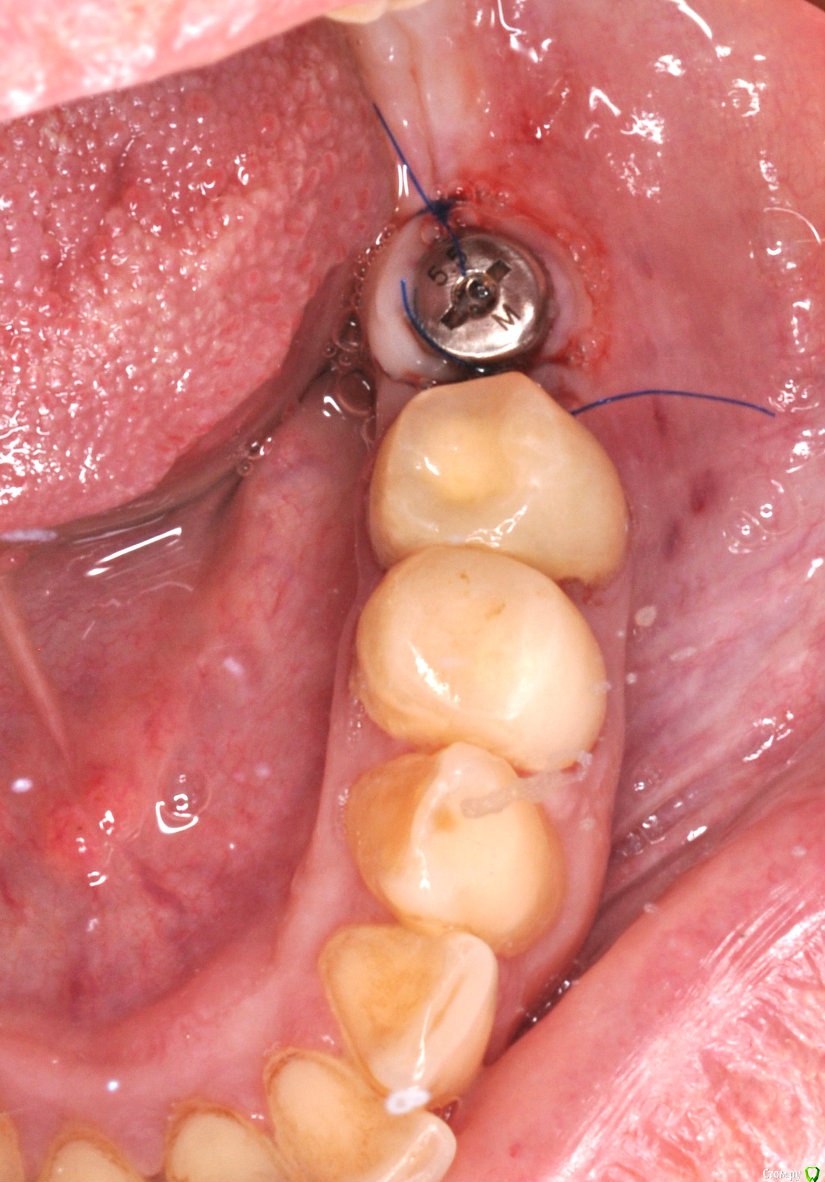

kriokov Опубликовано 7 сентября, 2016 Автор Поделиться Опубликовано 7 сентября, 2016 торк проверю - отпишусь торк 40, все штатно. Открывал без изысков. Крестально разрез, фдм, 2 шва унифлексом. Снимки свежие. 1 Ссылка на комментарий

kriokov Опубликовано 7 сентября, 2016 Автор Поделиться Опубликовано 7 сентября, 2016 (изменено) Без ССТ?да, там фдм стоит под 4мм, обьем мягкий есть, кератинизированная около 2 мм тоже есть. Решил сст не использовать. Заживет сфоткаю. Прсмотрим Изменено 7 сентября, 2016 пользователем kriokov 1 Ссылка на комментарий